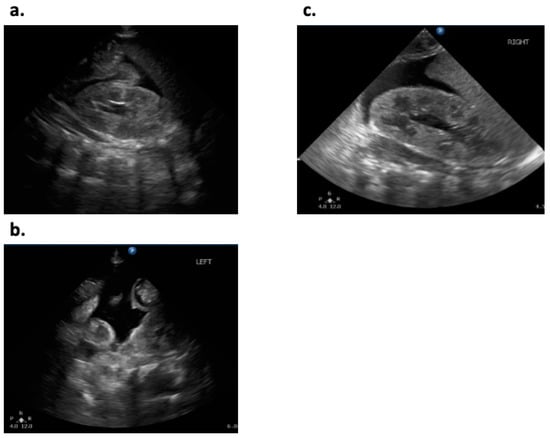

2. Case History